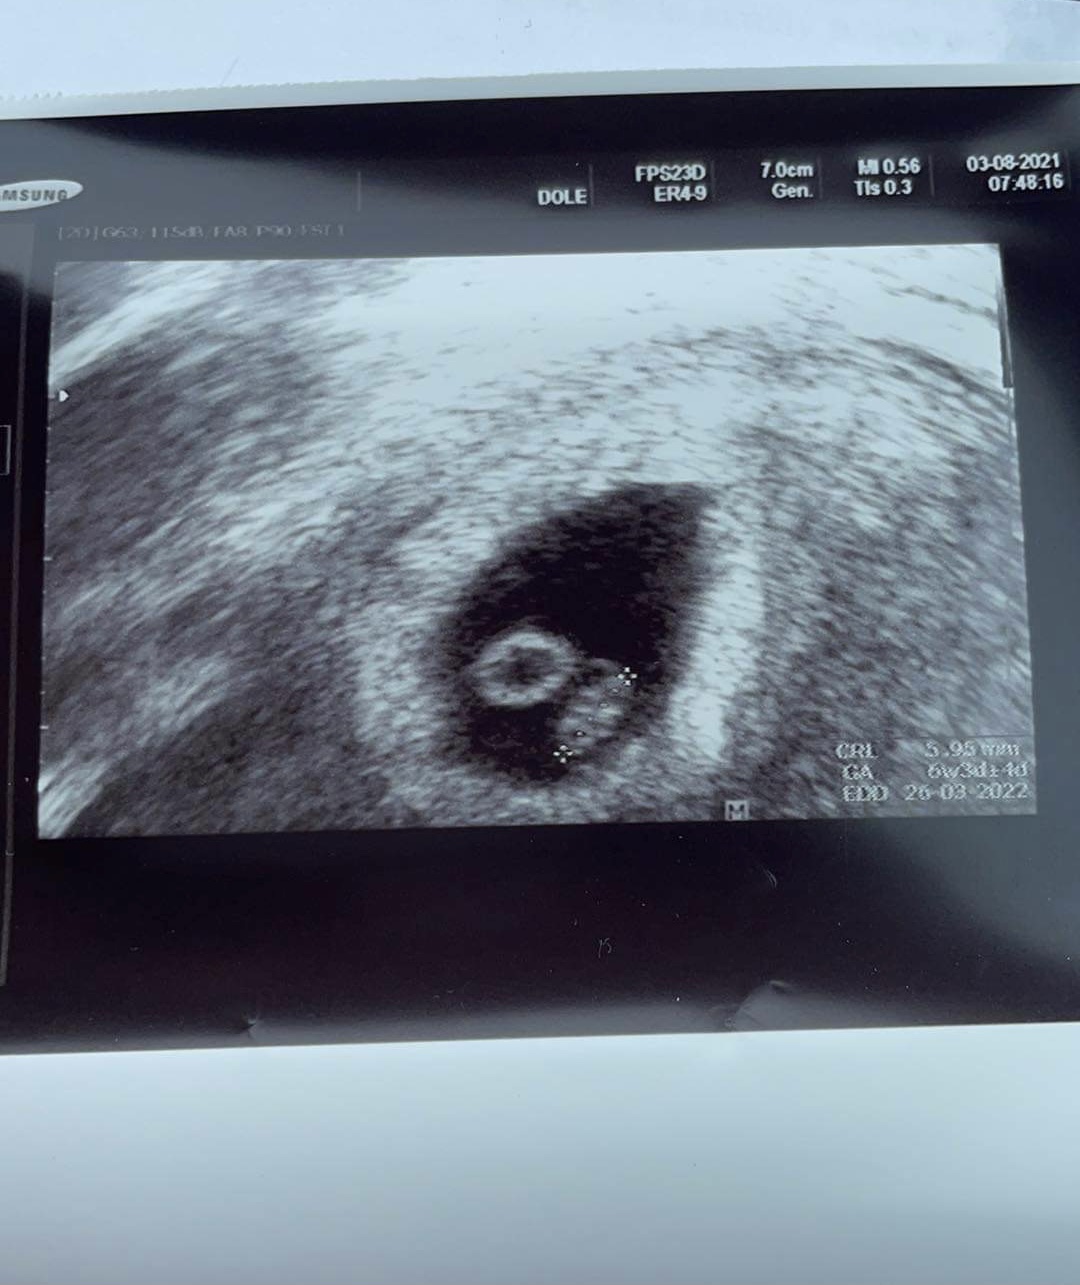

@katrinka233 Kati gratulujem 🙏😊 ja som 6tt akurát dnes bola na kontrolu a vraj všetko OK a už videl a potvrdil aj akciu srdiečka tak sa tiež už potichu vytesujem. Držím palce nech ide všetko hladko 💪